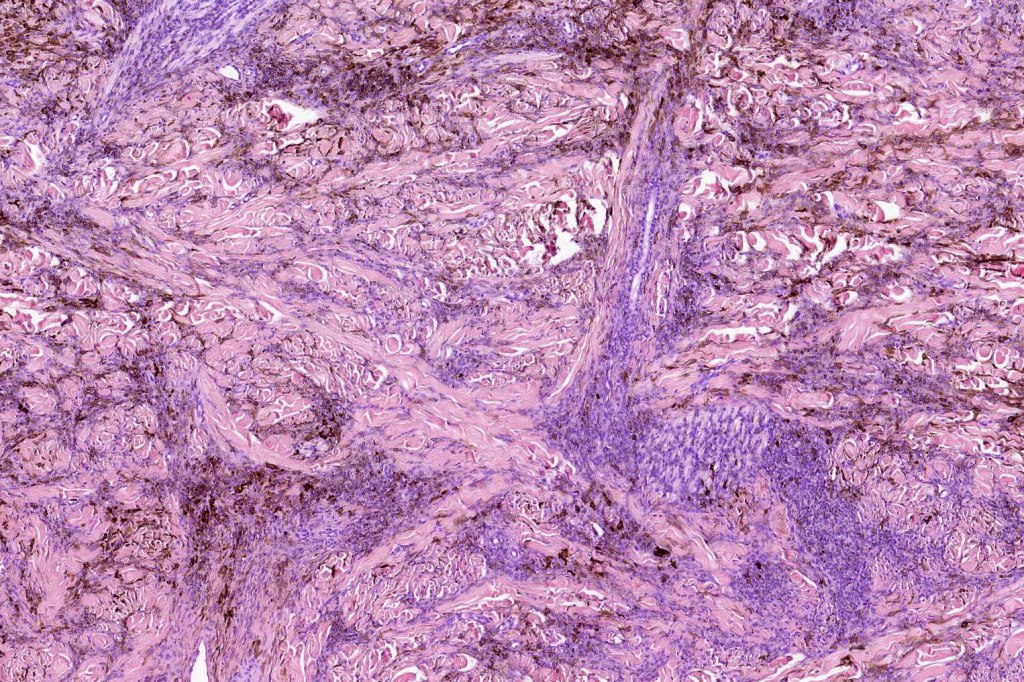

Combined common & deep penetrating nevus